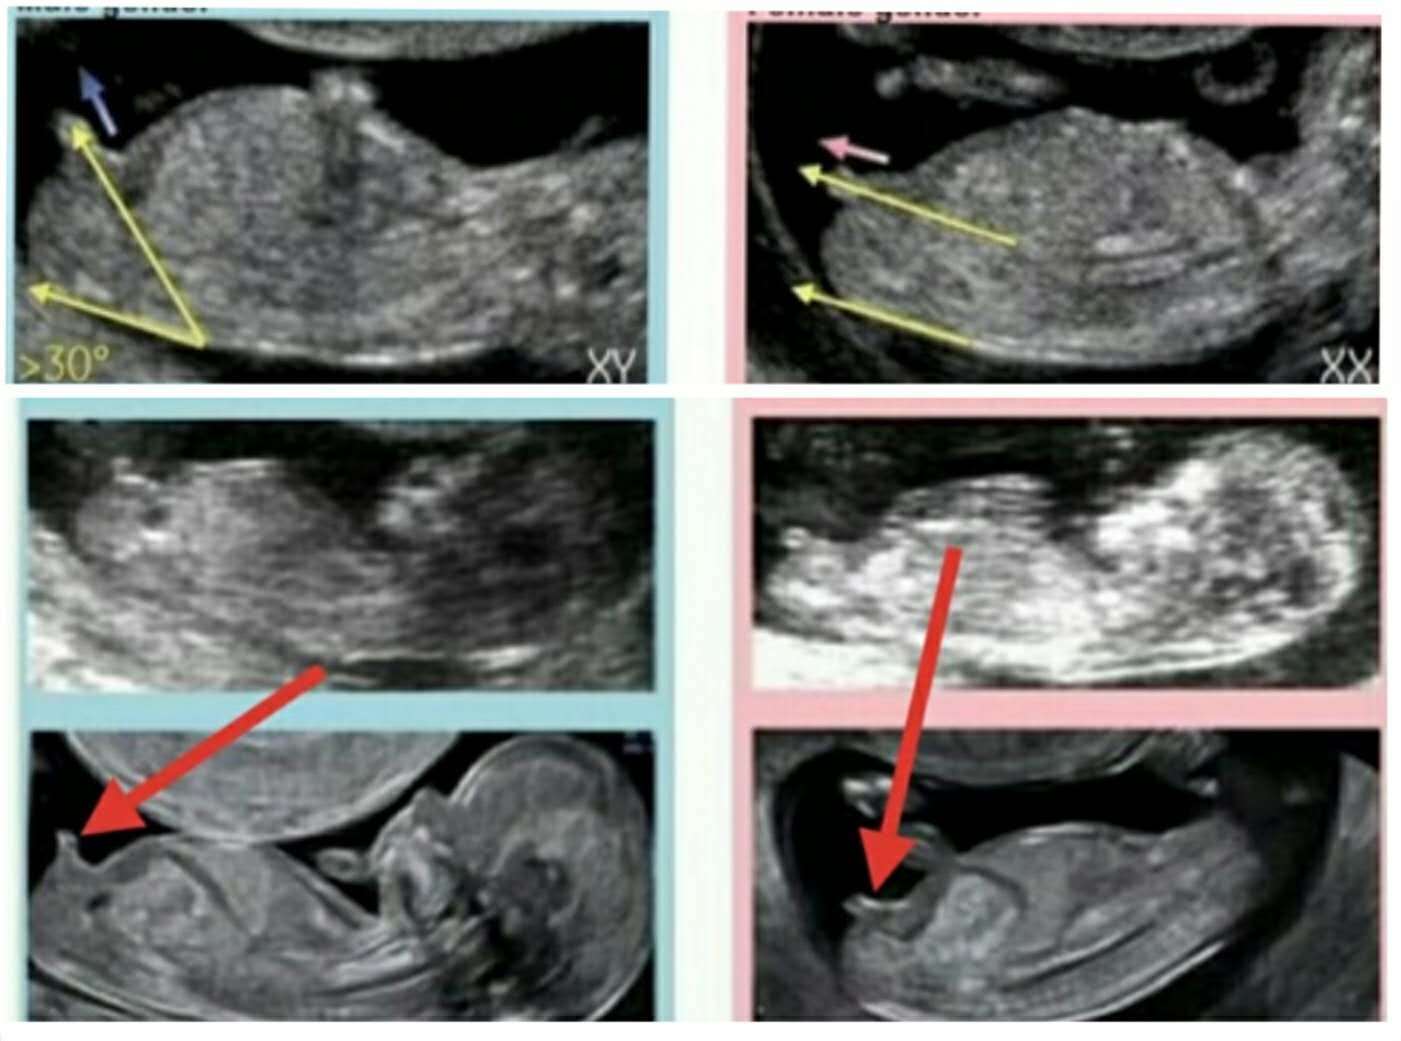

怀孕3个月男女胎儿差异大这个月胎儿从头到脚都有了宝宝的模样,身长7.5厘米,体重约30克。头大身小,大脑的发育比其它器官要快很多,每分钟产生脑细胞高达250000个,为了生个聪明宝宝,孕妈别忘了多吃富含DHA的鱼类及坚果、牛油果,蓝莓等富含花青色的水果。这几周是胎儿生殖qi的快速生长的黄金期,妊娠9周左右,就显示出男女差异了。如果是男孩,会在第10周形成前列腺,并在这个月末开始产生gao丸素。如果是女孩,会在月末形成卵巢。通过超声波观察生殖qi,能够提示是“小调皮”还是小棉袄。海外有些好奇心强的准爸爸准妈妈会专门照NT图来观察Nub的变化,他们认为Nub与背部平行的是小棉袄,与背部呈30°的为“小调皮”,如下图。

文章插图